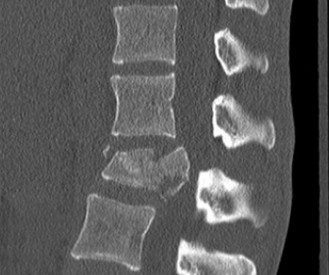

The diagnostic imaging workup for this patient spanned his initial presentation at age 15 and his subsequent return at age 20, providing a textbook illustration of the natural history of untreated isthmic spondylolysis. During his initial visit, standard weight-bearing anteroposterior (AP), lateral, and bilateral oblique radiographs of the lumbar spine were obtained. The lateral radiograph demonstrated a normal lumbar lordosis and preserved L5-S1 disc space height, with no evidence of anterior translation (spondylolisthesis). However, the oblique radiographs revealed the pathognomonic "collar on the Scotty dog" sign. The "Scotty dog" represents the posterior elements of the vertebra, where the nose is the transverse process, the eye is the pedicle, the front leg is the inferior articular process, and the neck is the pars interarticularis. A radiolucent line across the neck confirmed the presence of bilateral L5 pars defects.

Upon his return five years later, the imaging profile was drastically different. Standing lateral radiographs now revealed a Meyerding Grade 2 spondylolisthesis at L5-S1, indicating that the L5 vertebral body had translated anteriorly by 25% to 50% over the sacral promontory. Furthermore, there was a noticeable collapse of the L5-S1 intervertebral disc space, signifying advanced degenerative changes secondary to the altered biomechanics and chronic instability. We also meticulously measured the patient's spinopelvic parameters on a standing 36-inch scoliosis cassette. His Pelvic Incidence (PI) was measured at 65 degrees (high), which mathematically dictates a higher Sacral Slope (SS) and Pelvic Tilt (PT). A high PI is a known biomechanical risk factor for the progression of spondylolisthesis, as it creates a steeper lumbosacral shear angle, placing immense anterior translational force across the compromised L5-S1 segment.

To evaluate the neural elements and the soft tissue structures, a comprehensive MRI of the lumbar spine without contrast was obtained. The T2-weighted sagittal and axial sequences confirmed the Grade 2 anterolisthesis and demonstrated severe bilateral foraminal stenosis at L5-S1. The exiting L5 nerve roots were severely compressed between the hypertrophied, fibrocartilaginous pseudarthrosis tissue of the pars defect dorsally, and the bulging, degenerated L5-S1 disc and superior endplate of S1 ventrally. Furthermore, the MRI revealed Modic Type II changes (fatty replacement of the subchondral bone marrow) in the adjacent vertebral endplates, confirming chronic biomechanical stress and discogenic degeneration. The central canal remained relatively patent, which is characteristic of isthmic spondylolisthesis, as the posterior neural arch is left behind during the anterior translation of the vertebral body.